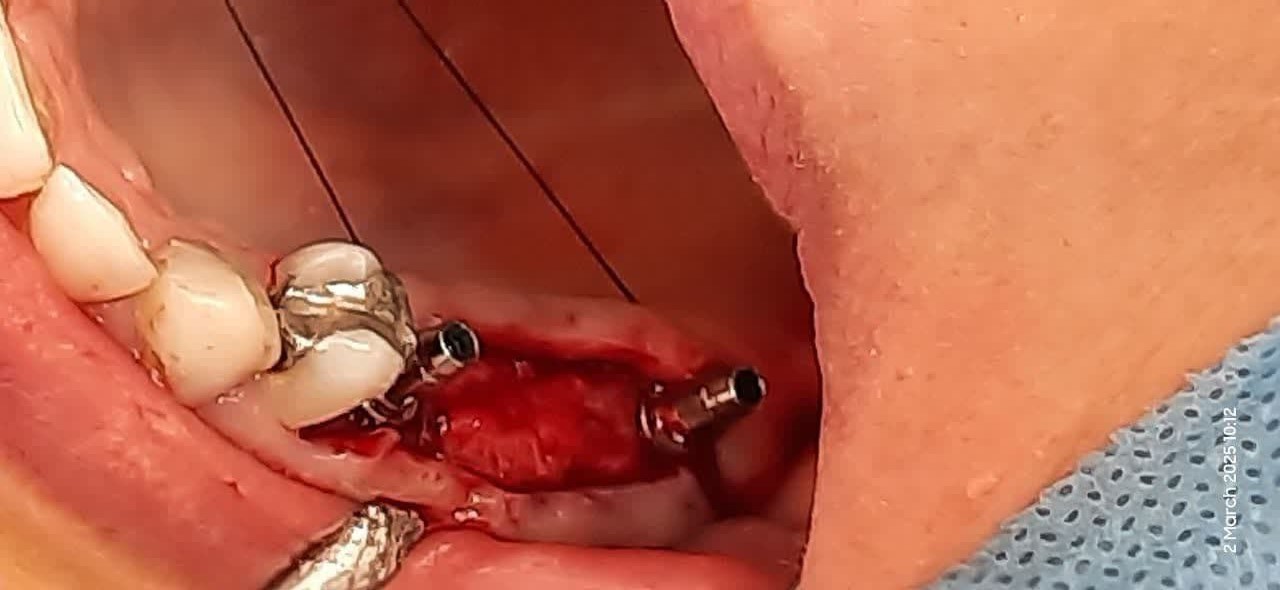

محل دقيق دريل کردن با استفاده از راهنماي ديجيتالي

ايمپلنتهاي قرار داده شده در محل دقيق و صحيح خود با استفاده از راهنما